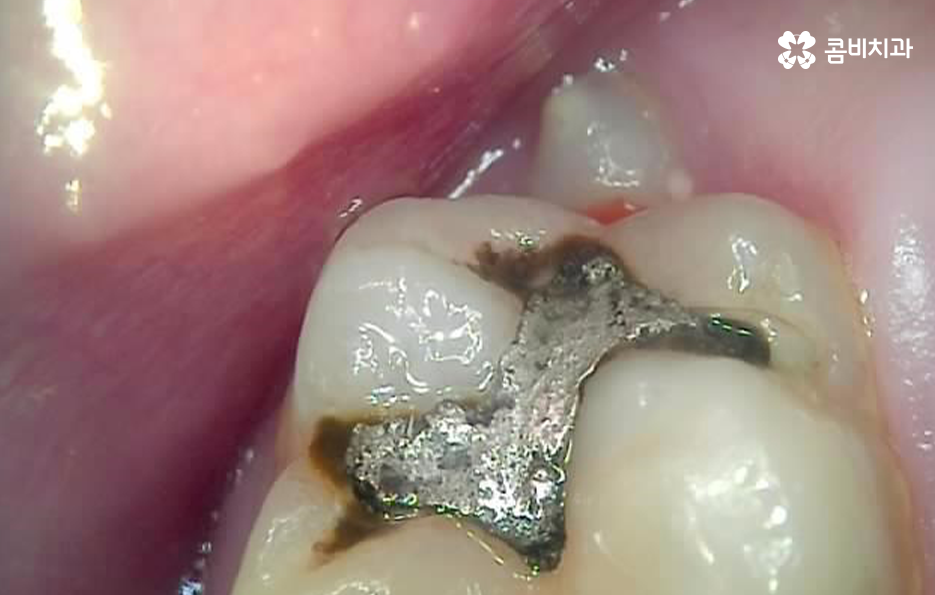

위 사례에서 보시는 것처럼 어금니 씹는 면에 이미 과거에 보철이나 아말감으로 치료 했던 흔적이 많이 남아 있어요. 어금니는 저작 기능에서 주된 역할을 하기 때문에 치아의 씹는 면에서 충치가 발생하기도 하고 나이가 들수록 치아의 마모로 인한 깨짐이나 균열로 인해 고생하는 분들도 많을 거예요

사진에서 보시는 것처럼 이미 과거에 어금니 충치치료 했던 부위에서 보철물 주변이 검게 변색이 되어 있고 보철물에 금이 간 모습도 확인할 수 있는데요

어금니 충치치료 후에도 꾸준히 보철물 상태를 확인하면서 2차 충치의 우려가 없는지 주기적으로 검진해야만 필요한 경우 보철물의 교체와 재치료를 통해 자연치아의 수명을 보존할 수 있어요

많은 분들이 오래된 보철물로 인해서 2차 충치의 문제가 발생되고 있으며 보철물 안에서 발생한 2차 충치의 경우 눈으로 확인이 어렵다는 점에서 아플 때까지 참다가 치료 시점을 놓치는 경우도 많을 거예요